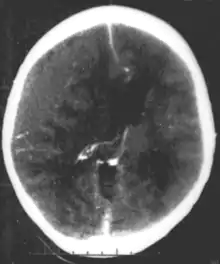

Epidural hematoma as seen on a CT scan with overlying skull fracture. Note the biconvex shaped collection of blood. There is also bruising with bleeding on the opposite side of the brain.

Epidural hematomas usually appear convex in shape because their expansion stops at the skull's sutures, where the dura mater is tightly attached to the skull. Thus, they expand inward toward the brain rather than along the inside of the skull, as occurs in subdural hematomas. Most people also have a skull fracture.[3]

Epidural hematomas may occur in combination with subdural hematomas, or either may occur alone.[11] CT scans reveal subdural or epidural hematomas in 20% of unconscious people.[16] In the hallmark of epidural hematoma, people may regain consciousness and appear completely normal during what is called a lucid interval, only to descend suddenly and rapidly into unconsciousness later. This lucid interval, which depends on the extent of the injury, is a key to diagnosing an epidural hematoma.[3]